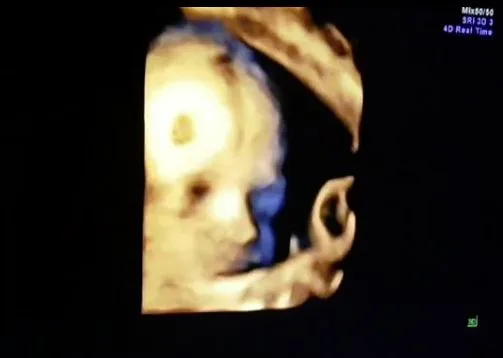

หลัง “คุณแม่นิวเคลียร์” อุ้มท้อง 10 เดือน เรียกได้ว่าเลยกำหนดเเล้ว แต่น้องไทก้า ก็ยังไม่คลอดซักที่ ล่าสุดวันนี้ สาวนิวออกมาโพสในไอจีส่วนตัวว่า “ให้เวลาไทก้าวันนี้วันสุดท้าย ไม่มาเองแม่ต้องผ่าแล้วพรุ่งนี้นะลูก เพื่อความปลอดภัยของหนู อุ้มมา10เดือนแล้ววววใจจริงไม่อยากผ่า แต่ด้วยหลายๆปัจจัยต้องผ่า เป็นกำลังใจให้แม่ด้วยน้า”